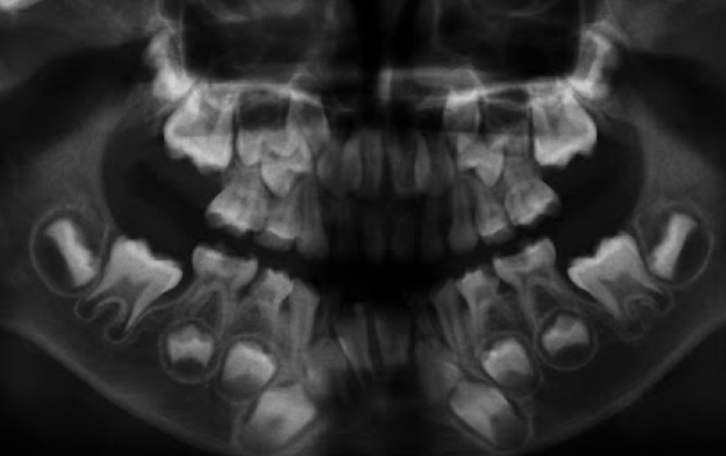

correction: patient is 6 as 1st molars erupted but incisors are yet to erupt when 7.